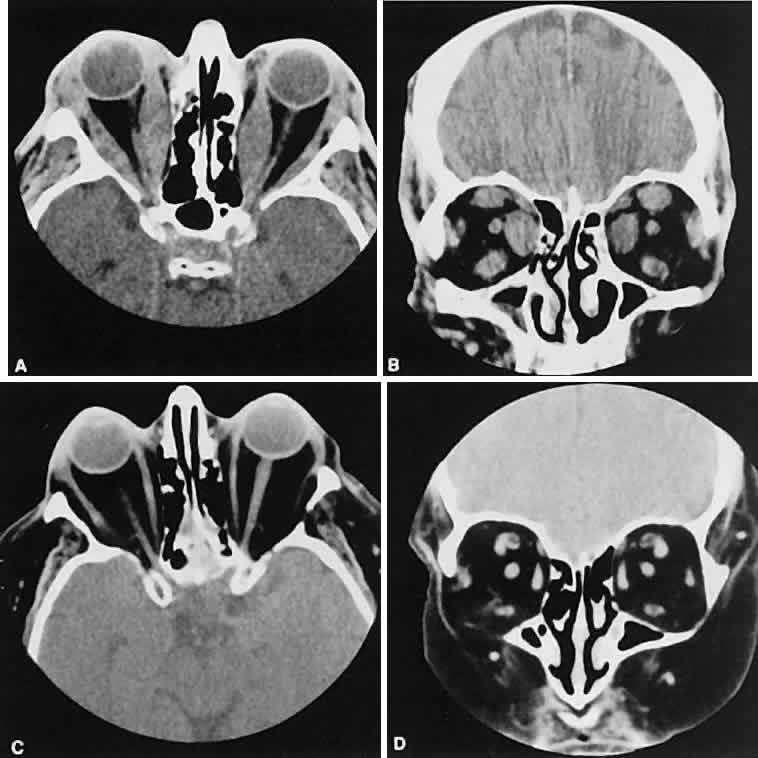

| In a qualitative way, CT scanning has redefined some of the concepts regarding

nonspecific orbital inflammations (orbital pseudotumor). We now

appreciate that any or all structures within the orbit or orbits may

be affected. Inflammation can be localized to an EOM (myositis), lacrimal

gland (dacryoadenitis), optic nerve sheath (perioptic neuritis), orbital

soft tissues (nonspecific inflammation), posterior scleritis, or

trochlea (trochleitis). There is no satisfactory explanation about

why or how this inflammation occurs and remains so localized, although

some types may be associated with various systemic diseases such as sarcoidosis, Wegener's

granulomatosis, or other vasculitic conditions. The CT characteristics of each subgroup are different and are considered separately. The nonspecific inflammation, if diffuse and acute, can affect the entire orbit with an amorphous infiltrate, which enhances with contrast (Fig. 4).13,14 The inflammation has been reported on occasion to spill over into the nasal15–18 and intracranial compartments.19–29 Chronic inflammation also may appear dense and relatively homogeneous. The margins may or may not be regular, and the lesions usually enhance with contrast. Changes in the adjacent bone, either sclerosis or hyperostosis or both, were seen on the CT in 30 (17%) of 176 patients with biopsy-proven pseudotumor.30

The CT evaluation of orbital myositis may show diffuse irregular enlargement of one or more EOMs; enlargement can be bilateral (Fig. 5). Incontradistinction to Graves' orbitopathy, involvement of the tendinous insertion and edema ofthe adjacent fat may be noted. Other conditions associated with EOM enlargement are listed in Table 2.31–33

Nonspecific inflammatory dacryoadenitis shows enlargement of the lacrimal gland, which typically molds to the shape of the globe (Fig. 6). The adjacent bone is normal, and contrast enhancement of the gland usually is fairly homogeneous. Bilateral involvement may be apparent with certain conditions such as Sjogren's syndrome, sarcoidosis, lymphoma, or even Graves' orbitopathy, although enlarged EOM in the latter condition might make this a more obvious diagnosis.

On most occasions, the inflammatory categories listed earlier are idiopathic and nonspecific. In-volvement of the adjacent paranasal sinuses should alert the clinician to the possibility of a systemic process such as Wegener's granulomatosis.34–38 Perioptic neuritis and trochleitis are the least common of the orbital inflammations. Clinically, perioptic neuritis shows signs of optic nerve dysfunction with pain and proptosis. The optic nerve may enhance, resembling acute optic neuritis39 or an optic nerve sheath meningioma.40 Inflammation of the trochlea presents with pain localized to the trochlea and can be associated with limitation of superior oblique muscle movement similar to a Brown's syndrome. Most patients are treated clinically without the benefit of CT scanning. One would expect an enhancing lesion centered on the trochlea. Calcification of the trochlea has been associated with advancing age; however, its presence, especially in those younger than 40 years of age, is strongly associated with diabetes.41 Graves' orbitopathy probably represents the most frequent cause of proptosis and EOM enlargement. The CT findings are fairly stereotyped and typically display various degrees of EOM enlargement (Fig. 7). The inferior rectus muscle usually is affected earliest, followed by the medial rectus, superior rectus, and finally the lateral rectus muscle. Rootman and colleagues13 noted more frequent involvement of the superior rectus/levator and medial rectus muscles than what had been reported previously with Graves' orbitopathy. These muscles can be affected in isolation, with the exception of the lateral rectus. To the best of our knowledge, isolated lateral rectus enlargement has not been reported in Graves' orbitopathy and in our experience usually is associated with a sphenoid wing meningioma. CT evidence of Graves' orbitopathy tends to be bilateral. Approximately 86% of patients with unilateral clinical findings have bilateral CT findings in our experience, which is consistent with the experience of others.42 Morphologically, the EOM belly is enlarged, with a gradual tapering toward and sparing of the tendinous portion of the muscle. Tendon involvement is a typical feature of orbital myositis. Tendon involvement helps to differentiate this lesion from Graves' orbitopathy, although Rootman and Nugent43 have noted a rare patient with Graves' orbitopathy with this finding. The muscle belly has a smooth contour with no edema of the adjacent orbital fat. We recently evaluated a patient with a referral diagnosis of Graves' orbitopathy. The patient was euthyroid but had severe orbital congestion typical of advanced Graves' orbitopathy. Imaging showed “dirty” orbital fat and lateral rectus muscle morphology that seemed atypical (Fig. 8). Biopsy specimen results showed a low-grade lymphoma. Hypertrophy of the medial rectus muscle can cause the medial wall to bow in toward the ethmoidal sinus from the chronic effects of pressure on the bone. The hypertrophied muscles also can give rise to a compressive optic neuropathy in the orbital apex as the enlarged muscles take their origin from the anulus of Zinn. Axial views of the apex show an apparent mass if the inferior rectus muscle is enlarged. It is imperative that additional views, sagittal or preferably coronal, be obtained to show the true nature of this apparent mass. Intracranial fat prolapse, seen by CT, may be another sign of optic neuropathy.44 An optic neuropathy also can be seen with relatively normal-sized EOM. An expanded fat compartment with optic nerve stretch has been associated with an optic neuropathy.45,46 Apical congestion/compression also may give rise to an enlarged SOV (see Table 1). If the veins appear asymmetric, the consideration of a carotid cavernous or dural sinus fistula should be entertained. Expansion of the orbital fat compartment also causes the orbital septum to bulge, an ancillary finding helpful in support of the radiographic picture of Graves' orbitopathy. We prefer CT scanning over MRI in the evaluation of patients with Graves' orbitopathy. Although there is no need to scan every patient, we do use imaging to corroborate the diagnosis of Graves' orbitopathy in instances of markedly asymmetric orbital involvement or any instance in which the diagnosis is in question. We also obtain a CT scan before orbital decompression to survey the paranasal sinus anatomy, to note the location of the infraorbital nerves giving an idea of how much floor is available for decompression, and, most important, to use the direct coronal views for inspection of the cribriform plate, which identifies patients at risk of having cerebrospinal fluid leaks.8 |